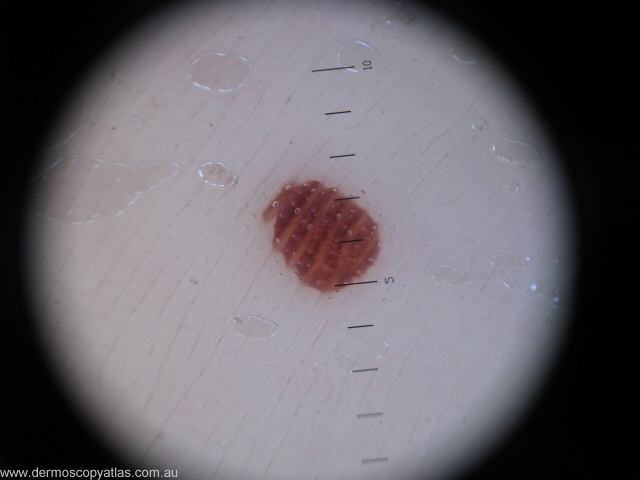

Case 8 13 Year old. Her mother is worried about this spot she noticed recently on her daughter's foot.

Question: Which of the following is true of this lesion. (one or more answers) It is most likely an acquired congenital naevus , It needs excision., It shows a parallel furrow pattern, It shows a parallel ridge pattern, The mother can be reassured it is benign